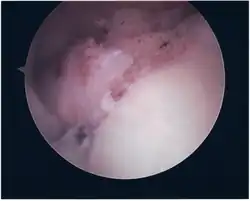

Twelve varieties of SLAP lesion have been described, with initial diagnosis by MRI or arthrography and confirmation by direct arthroscopy.[9]

Surgical treatment of SLAP tears has become more common in recent years. The success rate for repairing isolated SLAP tears is reported between 74-94%.[10] While surgery can be performed as a traditional open procedure, an arthroscopic technique[11] is currently favored being less intrusive with low chance of iatrogenic infection.[12]